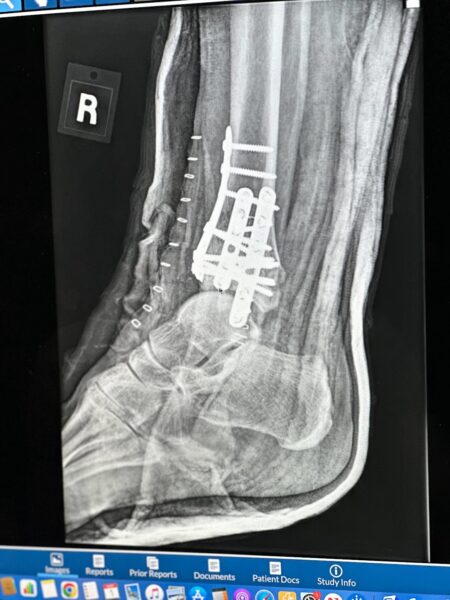

First Xray Post Surgery - February 2024